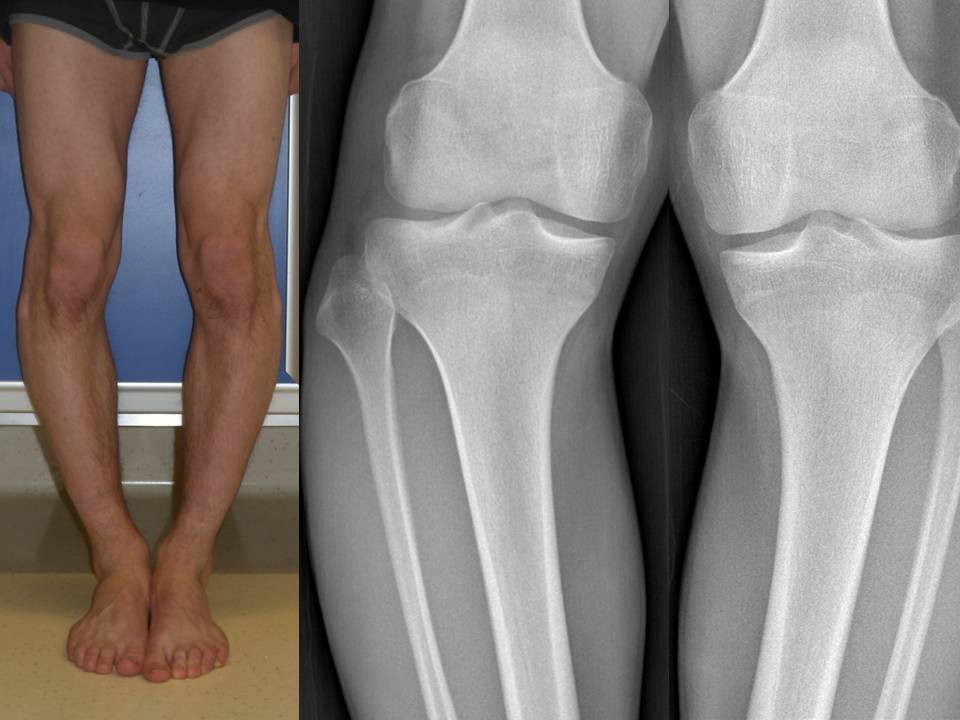

fig 6 A-B